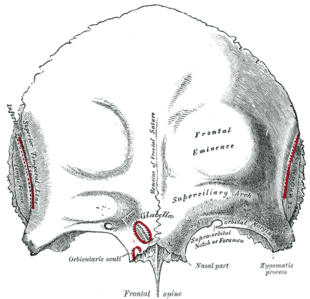

In some individuals the suture can persist (totally or partly) into adulthood, and in these cases it is referred to as a persistent metopic suture. The suture can either bisect the frontal bone and run from nasion to bregma or persist as a partial metopic suture (see image of frontal bone)[4] (where part of the suture survives and is connected to either bregma or nasion) or as an isolated metopic fissure. Persistent frontal sutures are of no clinical significance, although they can be mistaken for cranial fractures.[5] As persistent frontal sutures are visible in radiographs, they can be useful for the forensic identification of human skeletal remains. Persistent frontal sutures should not be confused with supranasal sutures (a small zig-zag shaped suture located at and/or immediately superior to the glabella).

| Outer surface of frontal bone, adult human skull. ("Remains of frontal suture" identified at center.) |